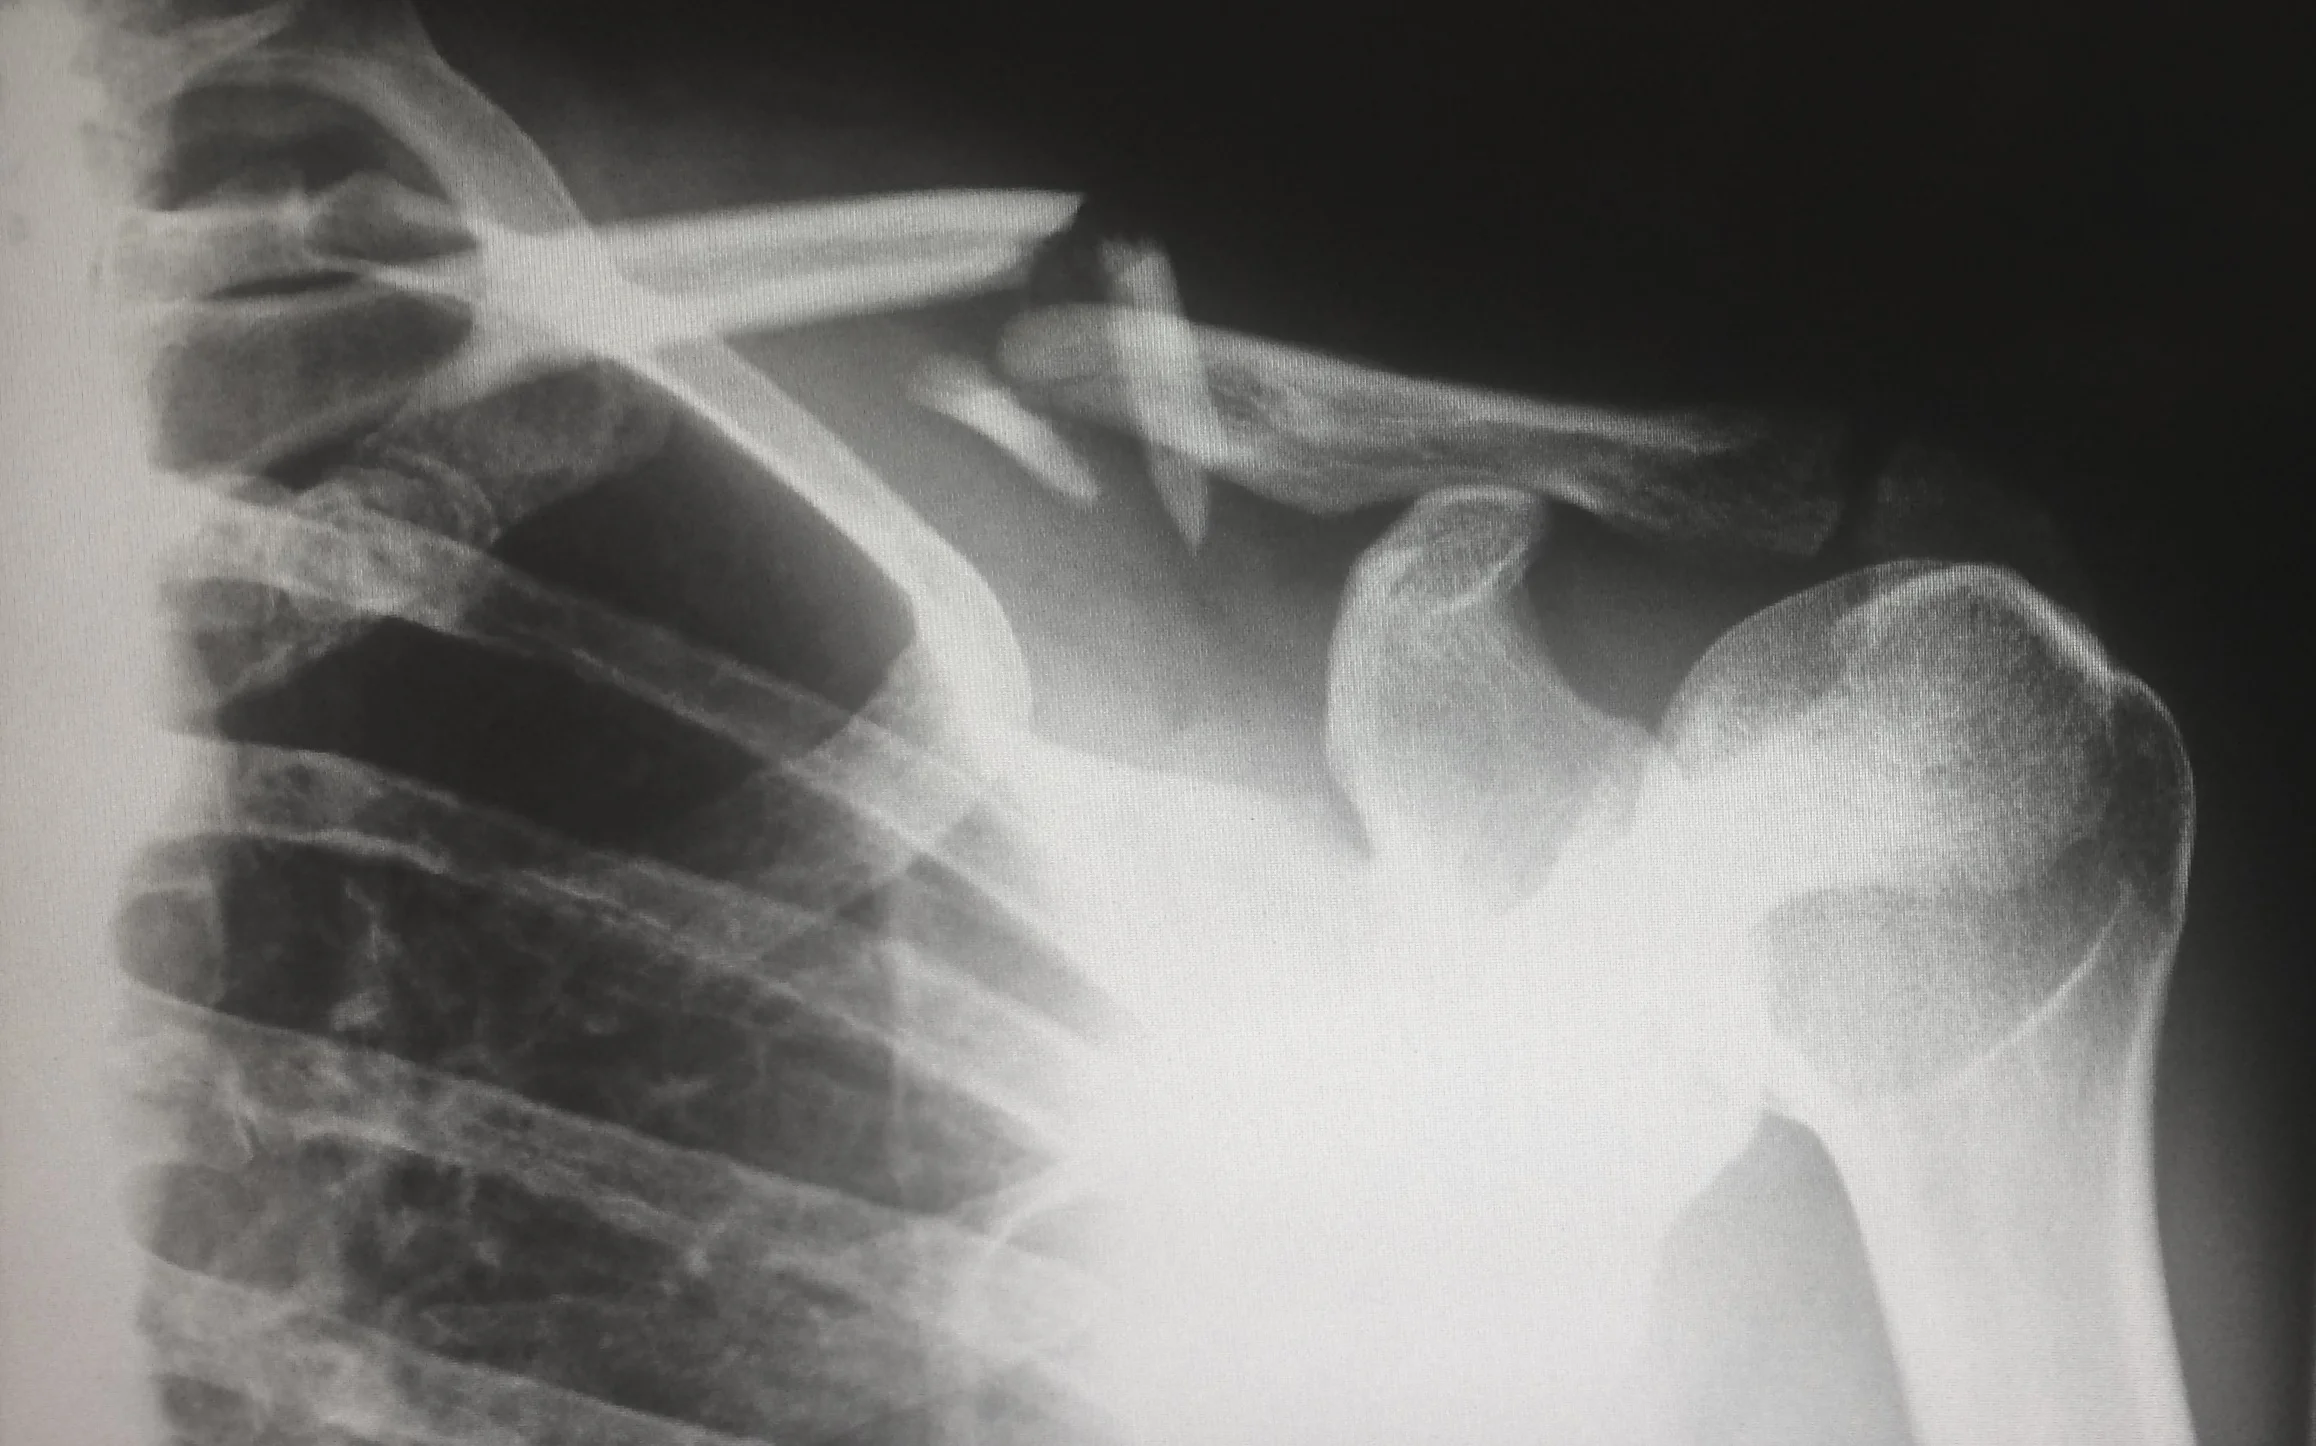

edited.jpg

[s]ustained a bodily injury which results in death; dismemberment; significant disfigurement or significant scarring; displaced fractures; loss of a fetus; or a permanent injury within a reasonable degree of medical probability, other than scarring or disfigurement. An injury shall be considered permanent when the body part or organ, or both has not healed to function normally and will not heal to function normally with further medical treatment. Ibid.